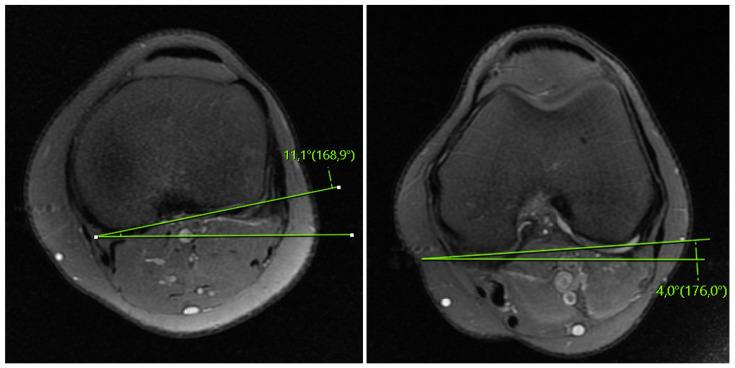

The aim of this study was to evaluate the presence of residual instability in the knee after ACL reconstruction through the analysis of MRI findings. This study included patients who underwent isolated ACL reconstruction between December 2019 and December 2021, and had preoperative and postoperative MRI, clinical scores, and postoperative isokinetic measurements. The anterior tibial translation (ATT) distance, coronal lateral collateral ligament (LCL) sign, and femorotibial rotation (FTR) angle were compared preoperatively and postoperatively. The correlation between the changes in preoperative-postoperative measurements and postoperative measurements with clinical scores and isokinetic measurements was examined. The clinical outcomes were compared based on the presence of a postoperative coronal LCL sign. Inclusion criteria were set as follows: the time between the ACL rupture and surgery being 6 months, availability of preoperative and postoperative clinical scores, and objective determination of muscle strength using isokinetic dynamometer device measurements. Patients with a history of previous knee surgery, additional ligament injuries other than the ACL, evidence of osteoarthritis on direct radiographs, cartilage injuries lower limb deformities, and contralateral knee injuries were excluded from this study. This study included 32 patients. After ACL reconstruction, there were no significant changes in the ATT distance (preoperatively: 6.5 ± 3.9 mm, postoperatively: 5.7 ± 3.2 mm) and FTR angle (preoperatively: 5.4° ± 2.9, postoperatively: 5.2° ± 3.5) compared to the preoperative measurements ( > 0.05). The clinical measurements were compared based on the presence of a postoperative coronal LCL sign (observed in 17 patients, not observed in 15 patients), and no significant differences were found for all parameters ( > 0.05). There were no observed correlations between postoperative FTR angle, postoperative ATT distance, FTR angle change, and ATT distance change values with postoperative clinical scores ( > 0.05). Significant correlations were observed between the high strength ratios generated at an angular velocity of 60° and a parameters FTR angle and ATT distance (-values: 0.028, 0.019, and r-values: -0.389, -0.413, respectively). Despite undergoing ACL reconstruction, no significant changes were observed in the indirect MRI findings (ATT distance, coronal LCL sign, and FTR angle). These results suggest that postoperative residual tibiofemoral rotation and tibial anterior translation may persist; however, they do not seem to have a direct impact on clinical scores. Furthermore, the increase in tibial translation and rotation could potentially negatively affect the flexion torque compared to the extension torque in movements requiring high torque at low angular velocities.

本研究旨在通过 MRI 检查结果分析评估 ACL 重建后膝关节的残余不稳定情况。本研究纳入了 2019 年 12 月至 2021 年 12 月期间接受单纯 ACL 重建的患者,且患者术前、术后均行 MRI、临床评分和术后等速测量。比较术前和术后胫骨前移(ATT)距离、冠状外侧副韧带(LCL)征和股骨胫骨旋转(FTR)角度。检查术前-术后测量值与术后临床评分和等速测量值之间的变化相关性。根据术后冠状 LCL 征的存在比较临床结果。纳入标准如下:ACL 破裂至手术的时间为 6 个月,术前、术后临床评分可用,使用等速测力计设备测量客观确定肌肉力量。排除既往膝关节手术史、除 ACL 以外的其他韧带损伤、直接 X 线片上骨关节炎证据、软骨损伤、下肢畸形和对侧膝关节损伤的患者。本研究共纳入 32 例患者。ACL 重建后,ATT 距离(术前:6.5 ± 3.9mm,术后:5.7 ± 3.2mm)和 FTR 角度(术前:5.4°±2.9°,术后:5.2°±3.5°)与术前测量值相比无显著变化(>0.05)。根据术后冠状 LCL 征的存在比较临床测量值(观察到 17 例,未观察到 15 例),所有参数均无显著差异(>0.05)。术后 FTR 角度、术后 ATT 距离、FTR 角度变化和 ATT 距离变化值与术后临床评分之间无观察到相关性(>0.05)。在角速度为 60°时产生的高力量比与 FTR 角度和 ATT 距离参数呈显著相关性(-值:0.028、0.019,r 值:-0.389、-0.413)。尽管进行了 ACL 重建,但间接 MRI 检查结果(ATT 距离、冠状 LCL 征和 FTR 角度)未见明显变化。这些结果表明,术后胫骨股骨旋转和胫骨前移可能持续存在,但它们似乎对临床评分没有直接影响。此外,与伸展扭矩相比,在需要低角速度高扭矩的运动中,胫骨平移和旋转的增加可能对屈曲扭矩产生负面影响。